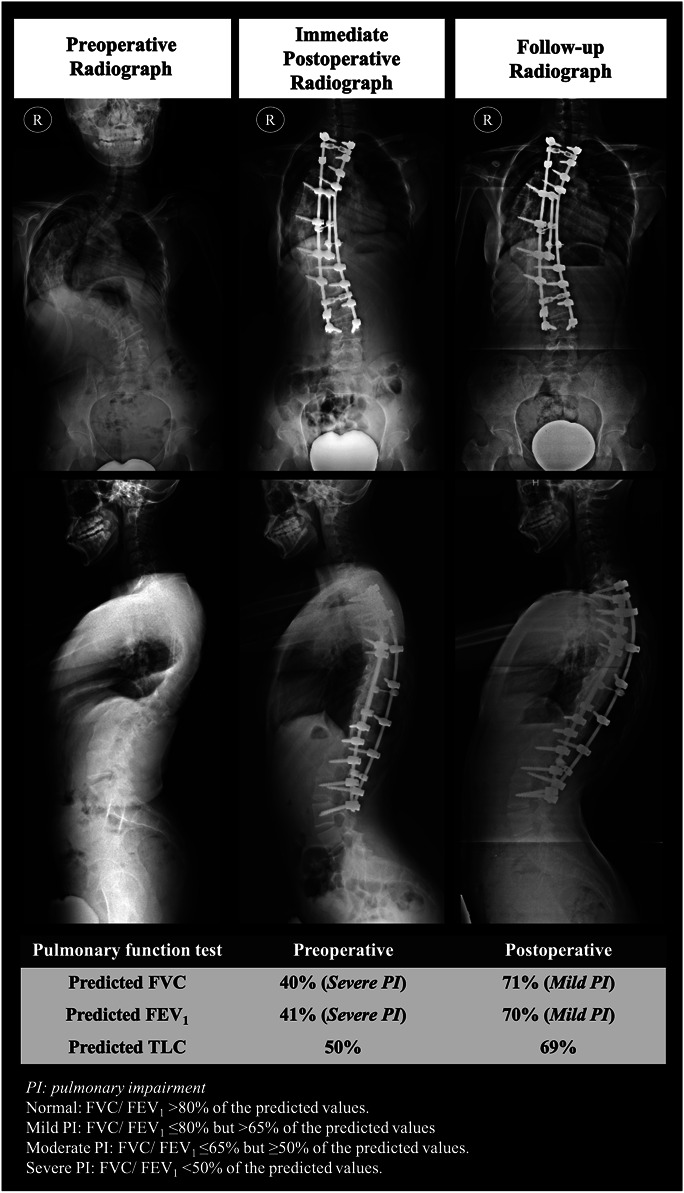

Methods: This study involved 18 severe AIS patients with major main thoracic curves (major Cobb angle ≥90°), who underwent posterior spinal fusion between 2019 and 2023, with a minimum 24-month follow-up. Primary PFT parameters measured preoperatively and at the most recent observation postoperatively were forced vital capacity (FVC), forced expiratory volume in one second (FEV1), and total lung capacity (TLC). Moderate to severe pulmonary impairment (MSPI) is defined as a predicted FVC/FEV1 of ≤65%. Patients were classified into having normal pulmonary function/mild pulmonary impairment (normal/mild PI) and MSPI. Postoperatively, patients were further categorized into having improved pulmonary function or stable pulmonary function based on the transition of their pulmonary function classification.

Results: The mean final follow-up duration was 37.9 ± 15.1 months. The major Cobb angle improved from 101.5° (93.0°-115.3°) to 45.0° (35.0°-58.0°) postoperatively (p < 0.001). There were increments of 14.7 ± 8.3% in predicted FVC and 15.2 ± 9.6% in predicted FEV1 postoperatively. The predicted FVC and FEV1 increased from 53.6 ± 11.9% and 50.1 ± 13.4% (preoperative) to 68.3 ± 7.9% and 65.3 ± 10.5% (postoperative), respectively (p < 0.001). Seven patients (50.0%) (based on FVC classification) and 6 patients (40.0%) (based on FEV 1 classification) with MSPI showed postoperative improvement in pulmonary function by transitioning to normal/mild PI. The remaining patients exhibited stable pulmonary function, and none experienced deterioration.

Conclusions: Patients with severe AIS demonstrated significant improvements in pulmonary function parameters after posterior spinal fusion. None experienced postoperative deterioration, whereas approximately 40.0% to 50.0% of those with MSPI improved to the normal/mild PI category.